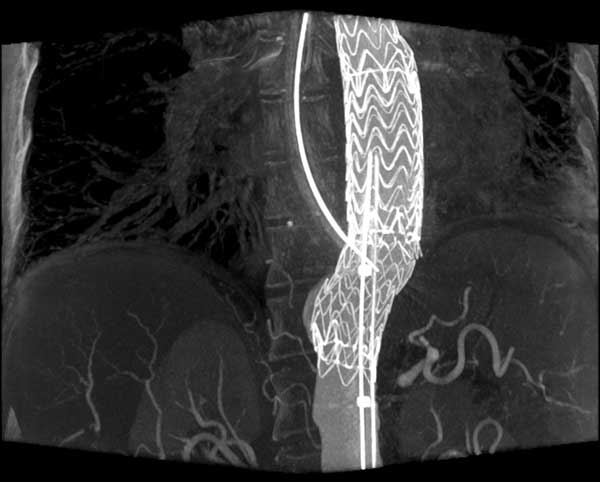

CT-like 3D imaging with the angiography system

Surgery very much depends on 3D visualization of the anatomy and therefore 3D CT-like imaging with the angiography system is an important feature, because it enables the surgeon to navigate in real time in 3D volumes. In principle, CT-like imaging of the heart is performed by one or two sweeps of up to 220° of the C-arm around the patient. During the rotation several hundred images are acquired and then reconstructed as a 3D volume. If the acquisition is gated by an ECG 3D volumes over time can be generated to depict the beating heart. Radiation dose is comparable to a conventional multi-slice CT. The OR staff can move out of the OR completely during a CT-like run, because it lasts only approximately 10 sec. Reconstruction is performed within one minute. Accurate information of the cardiac anatomy in the operating room supports planning of complex procedures like redo operations, surgery for complex congenital heart disease, transcatheter valve replacement. Segmentation of anatomical structures and overlay of the 3D volumes over live fluoroscopy (3D roadmap) enables the surgeon to virtually navigate in 3D anatomy (Figure 2). First investigations demonstrate the value of this new technology in transcatheter aortic valve replacement (13) (Figure 6), particularly with anatomical adjustable valve prosthesis as the Ventor Embracer valves. In pulmonary valve replacement the 3D valve anatomy in relation to the coronary artery anatomy is of great importance to avoid obstruction. In EVAR (5) endoleaks can be evaluated in the operating room and corrected, if deemed necessary.